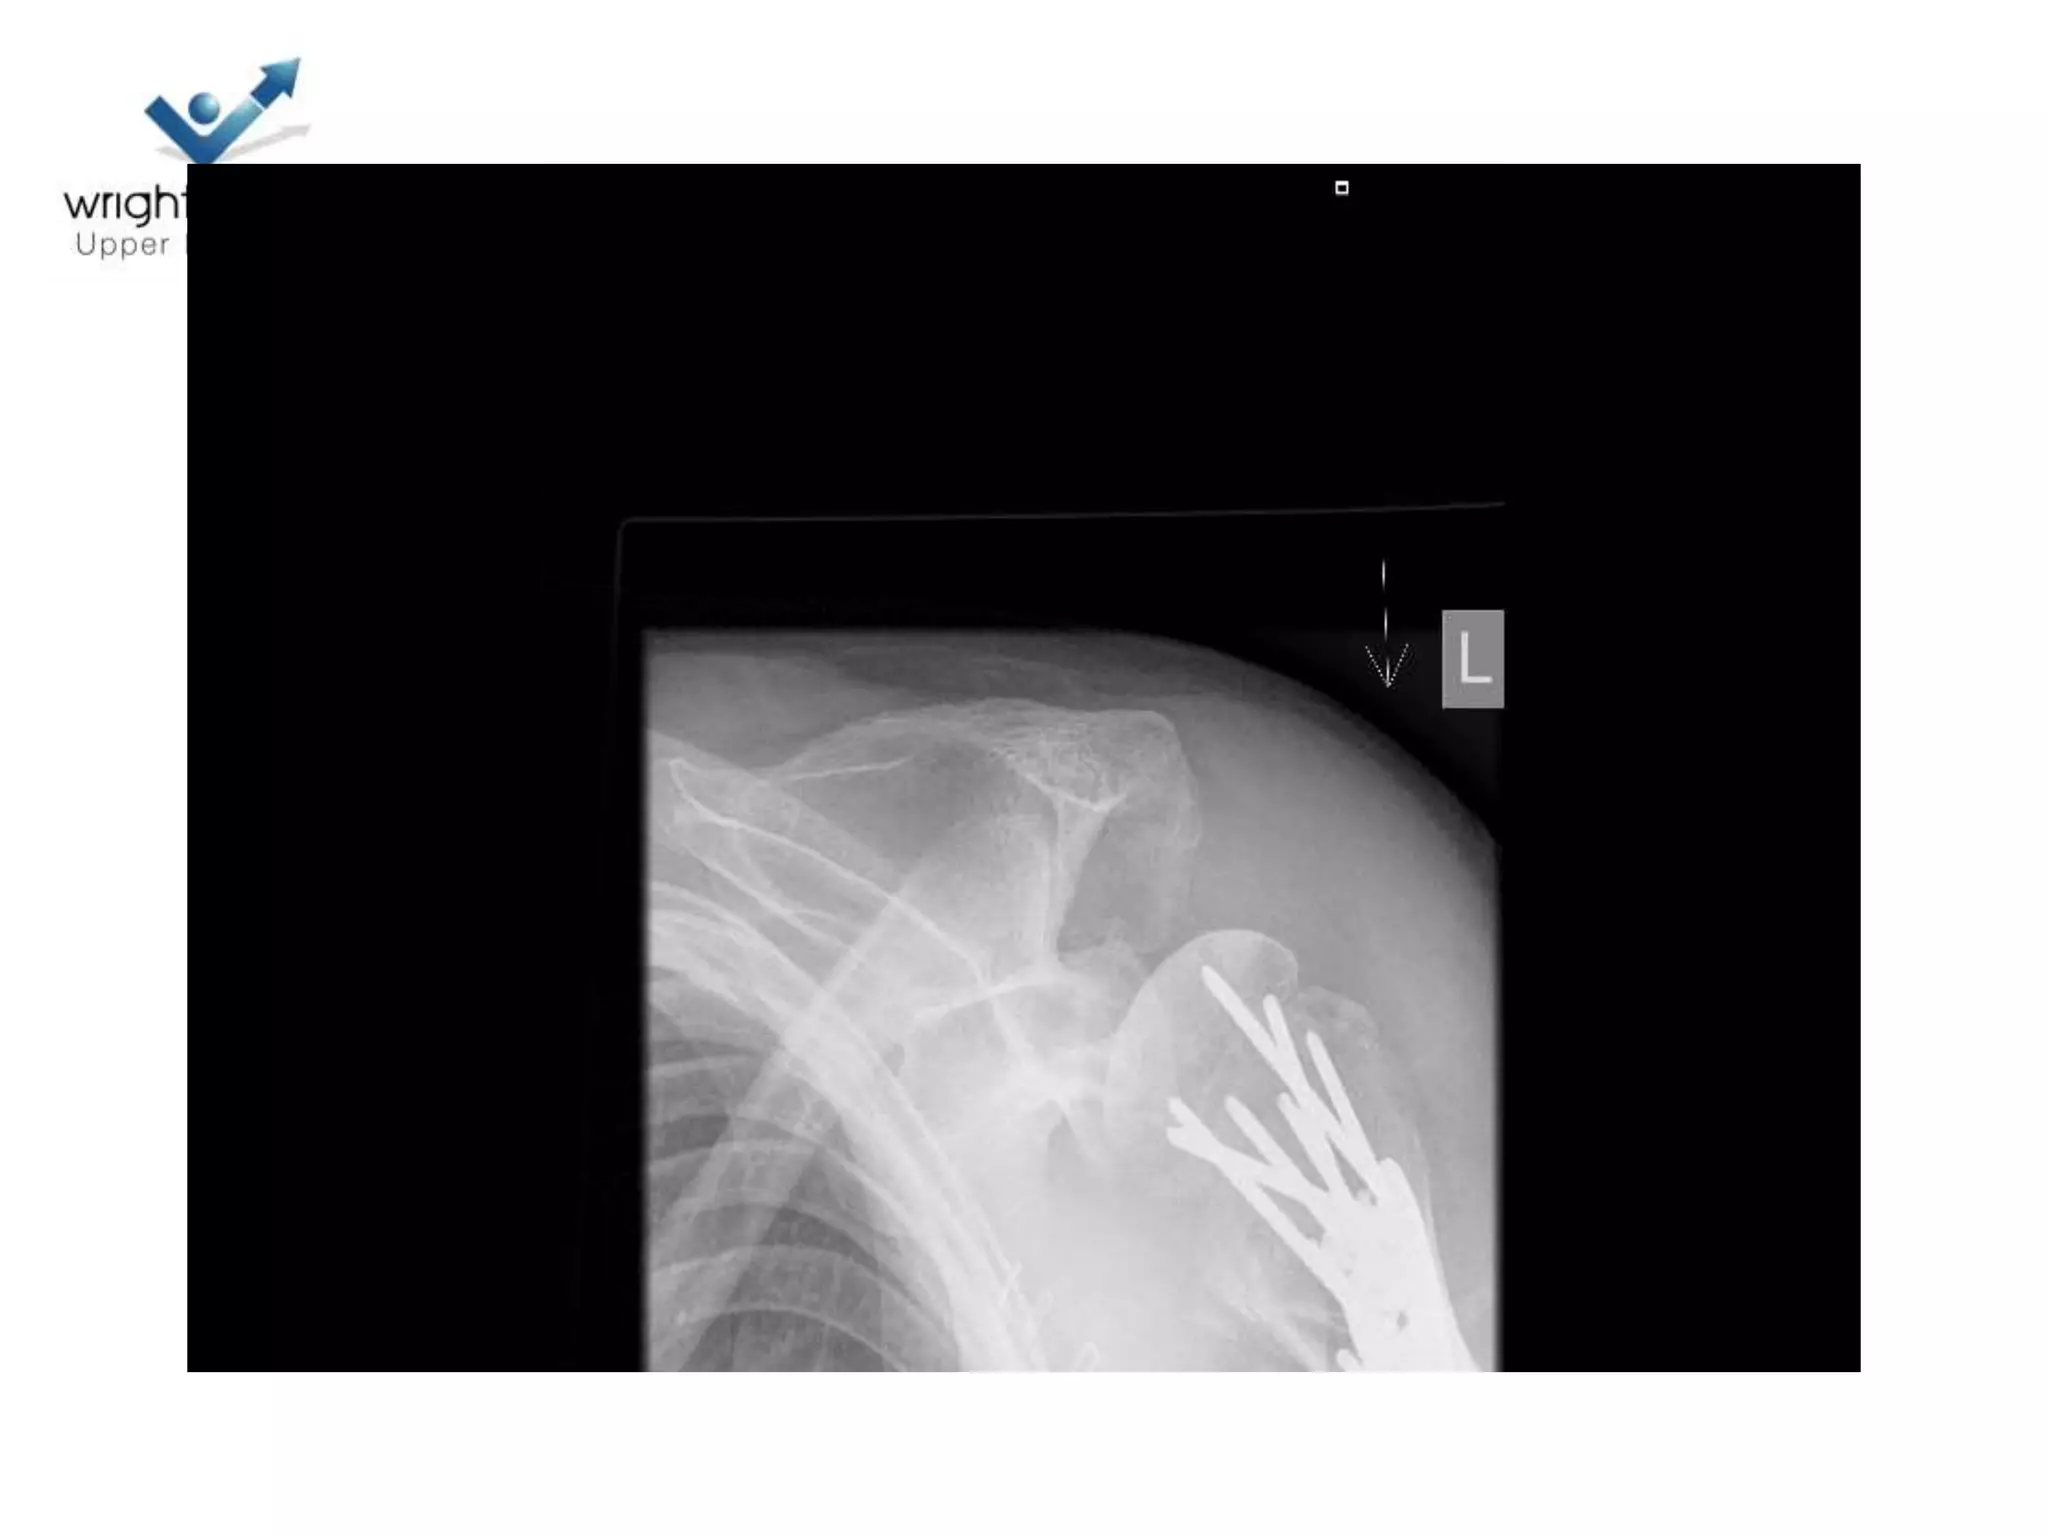

Locking plate; Tips

Locking plates: Tips

Locking plate: Tips

4 Next…